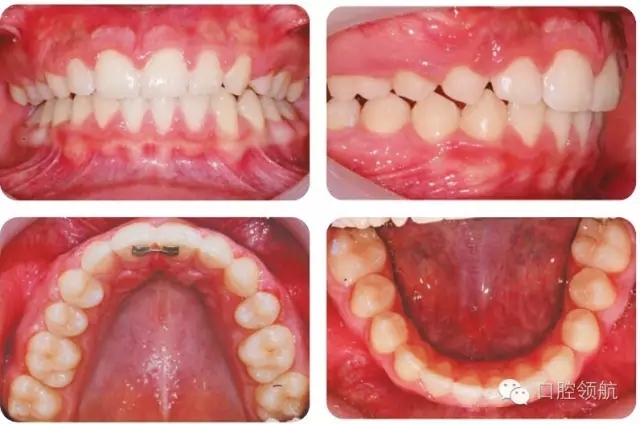

UR4應(yīng)如何改形模擬UR3?

UR4改形受到休息和功能狀態(tài)時(shí)上唇位置和上前牙外觀影響。休息時(shí)上唇線較低,切緣暴露很少,這樣齦緣高度不一致的情況不必特別考慮。因?yàn)榈谝磺澳パ澜h(yuǎn)中徑小于尖牙,托槽應(yīng)略靠遠(yuǎn)中使牙齒近中腭側(cè)旋轉(zhuǎn)。為了使前磨牙伸長(zhǎng),托槽應(yīng)放置在臨床牙冠中心略偏齦方,使頰尖位置與對(duì)側(cè)尖牙協(xié)調(diào)。如果伸長(zhǎng)前磨牙導(dǎo)致咬合早接觸,應(yīng)適當(dāng)降低舌尖。如果笑線較高,應(yīng)考慮壓入第一前磨牙或外科修整齦緣高度。前磨牙可以進(jìn)行貼面以更好地模擬尖牙外觀,調(diào)整牙尖垂直位置。圖2.45為最后的咬合像。